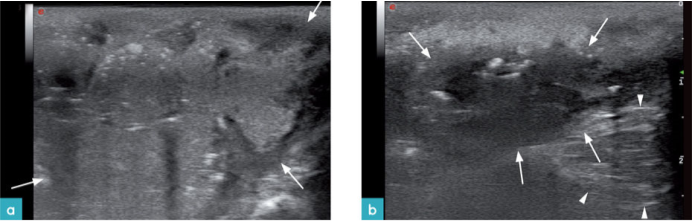

脓肿常由咬伤或异物造成。一般表现为囊腔样结构,有的脓肿边界不清晰,有的可见厚度不均的囊壁。根据腔内细胞含量不同,其回声可表现为无回声到高回声影像,囊内含有悬浮的颗粒样物质(图14.视频2)。

异物通常会引起脓肿。其影像表现与异物的形状,大小,声学特性有关,后方是否伴有声影与异物材质有关。户外猫身上常见散弹这样的异物,该异物的影像表现为高回声表面伴较弱声影(图15)。